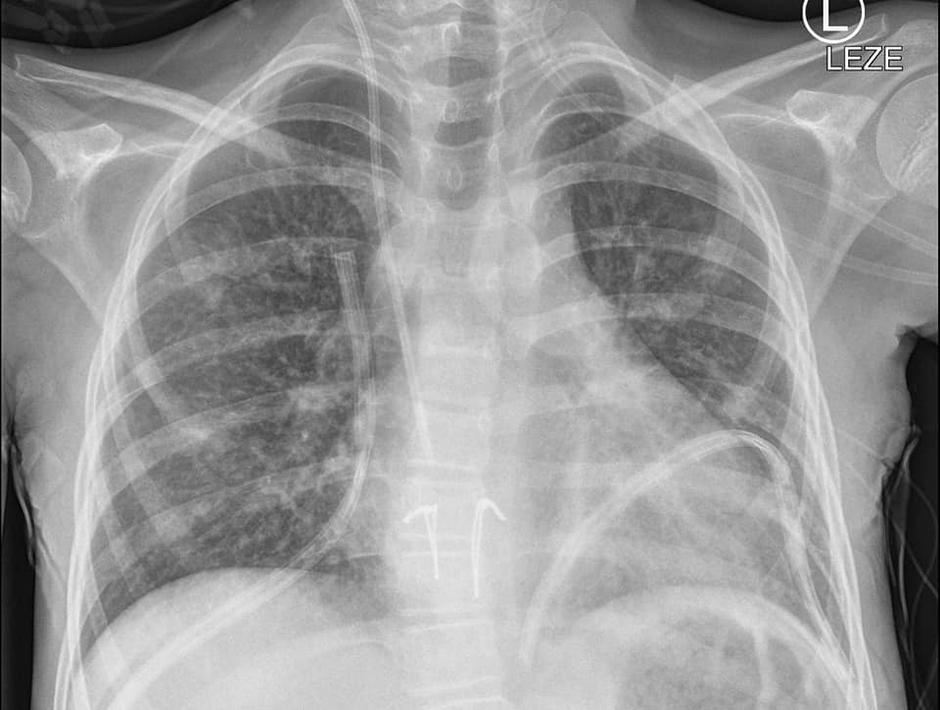

14. letno deklico s cistično fibrozo so operirali v noči na soboto in to je bila prva presaditev pljuč pri otroku pri nas. Deklica pa je že drugi dan po posegu samostojno zadihala z novimi pljuči in se sedaj odlično počuti.

Po besedah predstojnika, se je s presaditvijo že kar mudilo, stanje se je deklici poslabševalo, zato so transplantacijo morali opraviti v kakšnih treh mesecih ali morda pol leta. Najprej je bilo sicer predvideno, da bi jo operirali na Dunaju, a so tam kljub prošnjam sporočili, da nimajo zmogljivosti in presaditve ne morejo opraviti. "Imeli smo srečo, da so v hitrem času dobili pljuča primerno velikega otroka," je dodal. Pljuča so pripeljali s falconom iz tujine, v spremstvu treh kirurgov. Kot je pojasnil zdravnik, so takšni prevozi stresni, saj se lahko marsikaj zgodi na poti.

V tem primeru večjih zapletov ni bilo. Eurotransplant, organizacija, ki skrbi za izmenjavo in dodeljevanje pridobljenih organov, je dobila primeren organ, hitro za tem so obvestili starše in stekla je akcija. Deklica bo zdaj po optimalnem scenariju v bolnišnici še dva tedna. Gre namreč za veliko operacijo, kjer se marsikaj še lahko zgodi, zato je treba biti pozoren na vsako podrobnost. Da se bo lahko vrnila v normalno življenje, pa bo verjetno trajalo še nekaj mesecev.